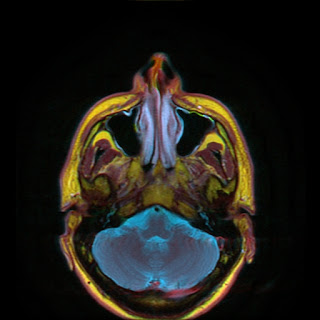

Color MRI of the Neck

- InPhase +C T1 IDEAL in Red channel

- InPhase T2 IDEAL in Green channel

- WATER T2 IDEAL in Blue channel.